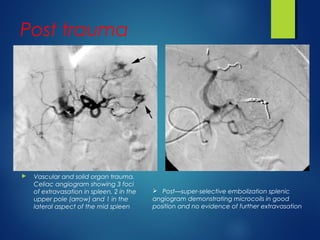

 Vascular and solid organ trauma.

Celiac angiogram showing 3 foci

of extravasation in spleen, 2 in the

upper pole (arrow) and 1 in the

lateral aspect of the mid spleen

 Post—super-selective embolization splenic

angiogram demonstrating microcoils in good

position and no evidence of further extravasation